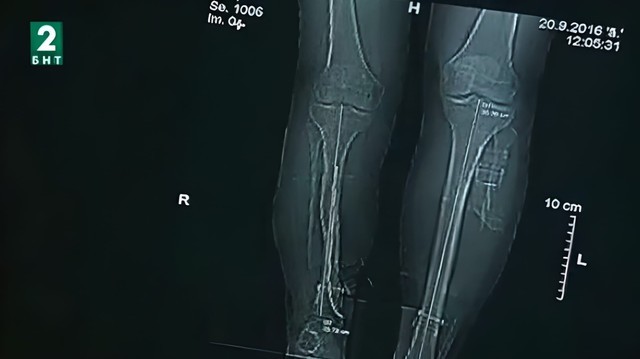

Ортопедът Мирослав Живков от Варненската болница "Света Анна" осъществява своята мечта _ да специализира ортопедия, за да помага на хората да стъпят отново на краката си. Особено ценна е помощта му за бебета и малки деца, родени с криво стъпало. "Прохождането" е филм-алегория за израстването на самия лекар, за изучаването на нови методи и прилагането на световни технологии както в лечението на кривото стъпало, така и вудължаването на крайници и други детски малформации.